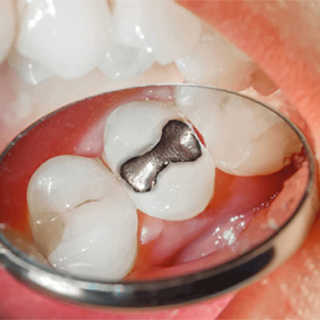

¿CUÁNDO ES MEJOR UNA INCRUSTACIÓN DENTAL QUE UN EMPASTE?

Cuando un diente sufre una caries extensa o una fractura, una de las dudas más frecuentes en consulta es si basta con un empaste o si conviene una solución más...